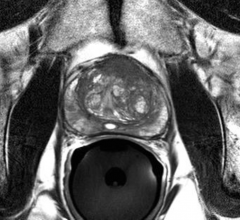

News and new technology innovations concerning how imaging technology can help diagnose and treat prostate cancer can be found on this channel.